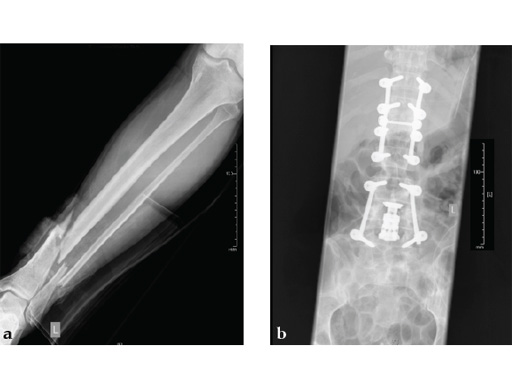

Case provided by Michael Raschke, Münster, Germany

Case 2: Grade II open distal tibial fracture in a polytraumatized 52-year-old man.